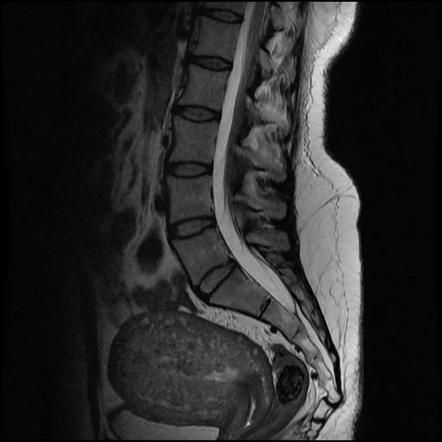

Coccydynia refers to the pain in the tailbone. The common causes of coccydynia are: - Childbirth It is one of the most common causes. Overstretching of ligaments and muscles during childbirth can result in persistent pain. - Trauma Falling backward or hard impact during sports or accidents can cause pain in tailbone. - Repetitive Strain Injury Any activity that can put tailbone under constant stress can result in coccydynia. The examples of such activities are cycling and rowing. - Poor posture Sitting in an inappropriate posture, especially for longer duration of time, can severely impact the tailbone. - Obesity Obesity puts excessive pressure on coccyx. - Underweight Lack of buttock fat can cause injury to coccyx secondary to repetitive rubbing. - Ageing Wear and tear in ageing process cause loss of cartilage discs that hold the coccyx in its place. - Infection Pilonidal abscess can cause pain in tailbone. - Cancer Primary or metastatic cancer can involve coccyx, thereby causing coccydynia. Reference: https://www.nhs.uk/conditions/tailbone-pain-coccydynia/causes/ Image via: https://radiopaedia.org/articles/coccydynia?lang=gb